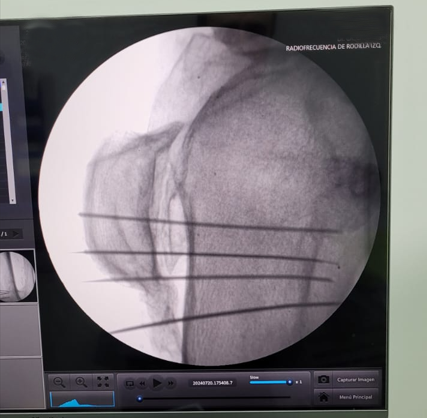

En Tidol tratamos el caso de un paciente de 90 años, con artrosis severa de rodilla izquierda.

El paciente presentaba limitaciones de reemplazo total de rodilla y no se le podía realizar la cirugía por osteoporosis y comorbilidad; por lo que se decidió realizar tratamiento con radiofrecuencia de los nervios geniculados.

Previo al tratamiento, el paciente no podía caminar debido a dolor; luego del tratamiento mejoró notablemente su sintomatología, comenzando a realizar la rehabilitación con fisioterapia dirigida.